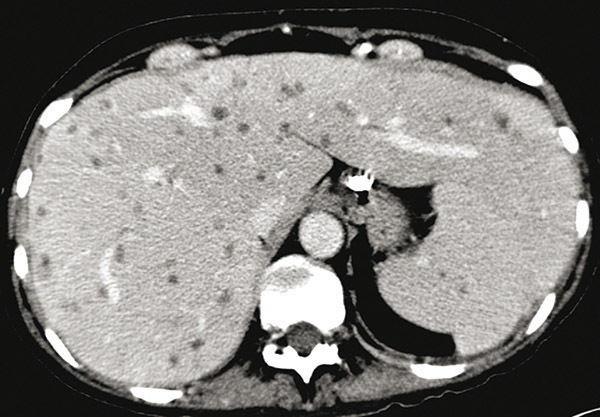

© Sylvain Poirée - La Revue du Praticien Tomodensitométrie abdominale après injection de produit de contraste montrant de multiples nodules hépatiques et spléniques.